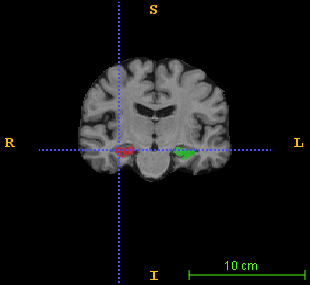

Over the past decades, state-of-the-art medical image segmentation has heavily rested on signal processing paradigms, most notably registration-based label propagation and pair-wise patch comparison, which are generally slow despite a high segmentation accuracy. In recent years, deep learning has revolutionalized computer vision with many practices outperforming prior art, in particular the convolutional neural network (CNN) studies on image classification. Deep CNN has also started being applied to medical image segmentation lately, but generally involves long training and demanding memory requirements, achieving limited success. We propose a patch-based deep learning framework based on a revisit to the classic neural network model with substantial modernization, including the use of Rectified Linear Unit (ReLU) activation, dropout layers, 2.5D tri-planar patch multi-pathway settings. In a test application to hippocampus segmentation using 100 brain MR images from the ADNI database, our approach significantly outperformed prior art in terms of both segmentation accuracy and speed: scoring a median Dice score up to 90.98% on a near real-time performance (<1s).